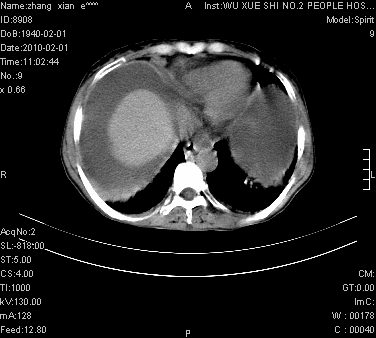

标题: CT24434:70岁 女 腹胀,腹水原因待查 [打印本页]

标题: CT24434:70岁 女 腹胀,腹水原因待查

大量腹水,脾脏囊性占位,子宫颈占位,右侧腹股沟淋巴结肿大,建议+c,先查妇科。

大量腹水,脾囊肿可能性大,建议增强

腹盆腔大量积液,子宫增大,子宫颈增大外形不规则,内见低密度影,膀胱后壁显示不清,右腹股沟肿大淋巴结,脾脏囊性占位,子宫颈占位,子宫颈癌?建议增强。

大量腹水,右肾、脾囊肿可能性大          考虑左侧附件区占位,建议增强